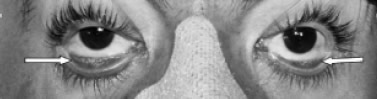

Masculino de 36 años, previamente sano, ocupación policía. Ingresó posterior a herida por proyectil de arma de fuego en pierna izquierda que condicionó fractura de peroné (Figura 1). Presentó crisis convulsivas tónico-clónicas generalizadas, estado confusional, dificultad respiratoria e hipoxemia, por lo que se ingresó a la UTI. A la exploración física con FC de 130/m, FR de 35/m, PA de 100/60, SatO2 al aire ambiente al 70%, Temperatura de 38 ºC. Con estertores crepitantes e hipoaereación bibasal de predominio izquierdo. Presencia de petequias a nivel conjuntival (Figura 2). En la citometría hemática con trombocitopenia de 150,000/mm3. En la Rx de tórax con infiltrado intersticial bibasal de predominio izquierdo (Figura 3). En la angiotomografía computada de tórax se observó infiltrado intersticial y áreas de condensación de predominio basal y no se observaron coágulos en el sistema arterial pulmonar. La resonancia magnética cerebral con imágenes hiperintensas corticales bilaterales (Figura 4).

Figura 2. Petequias conjuntivales (flechas).